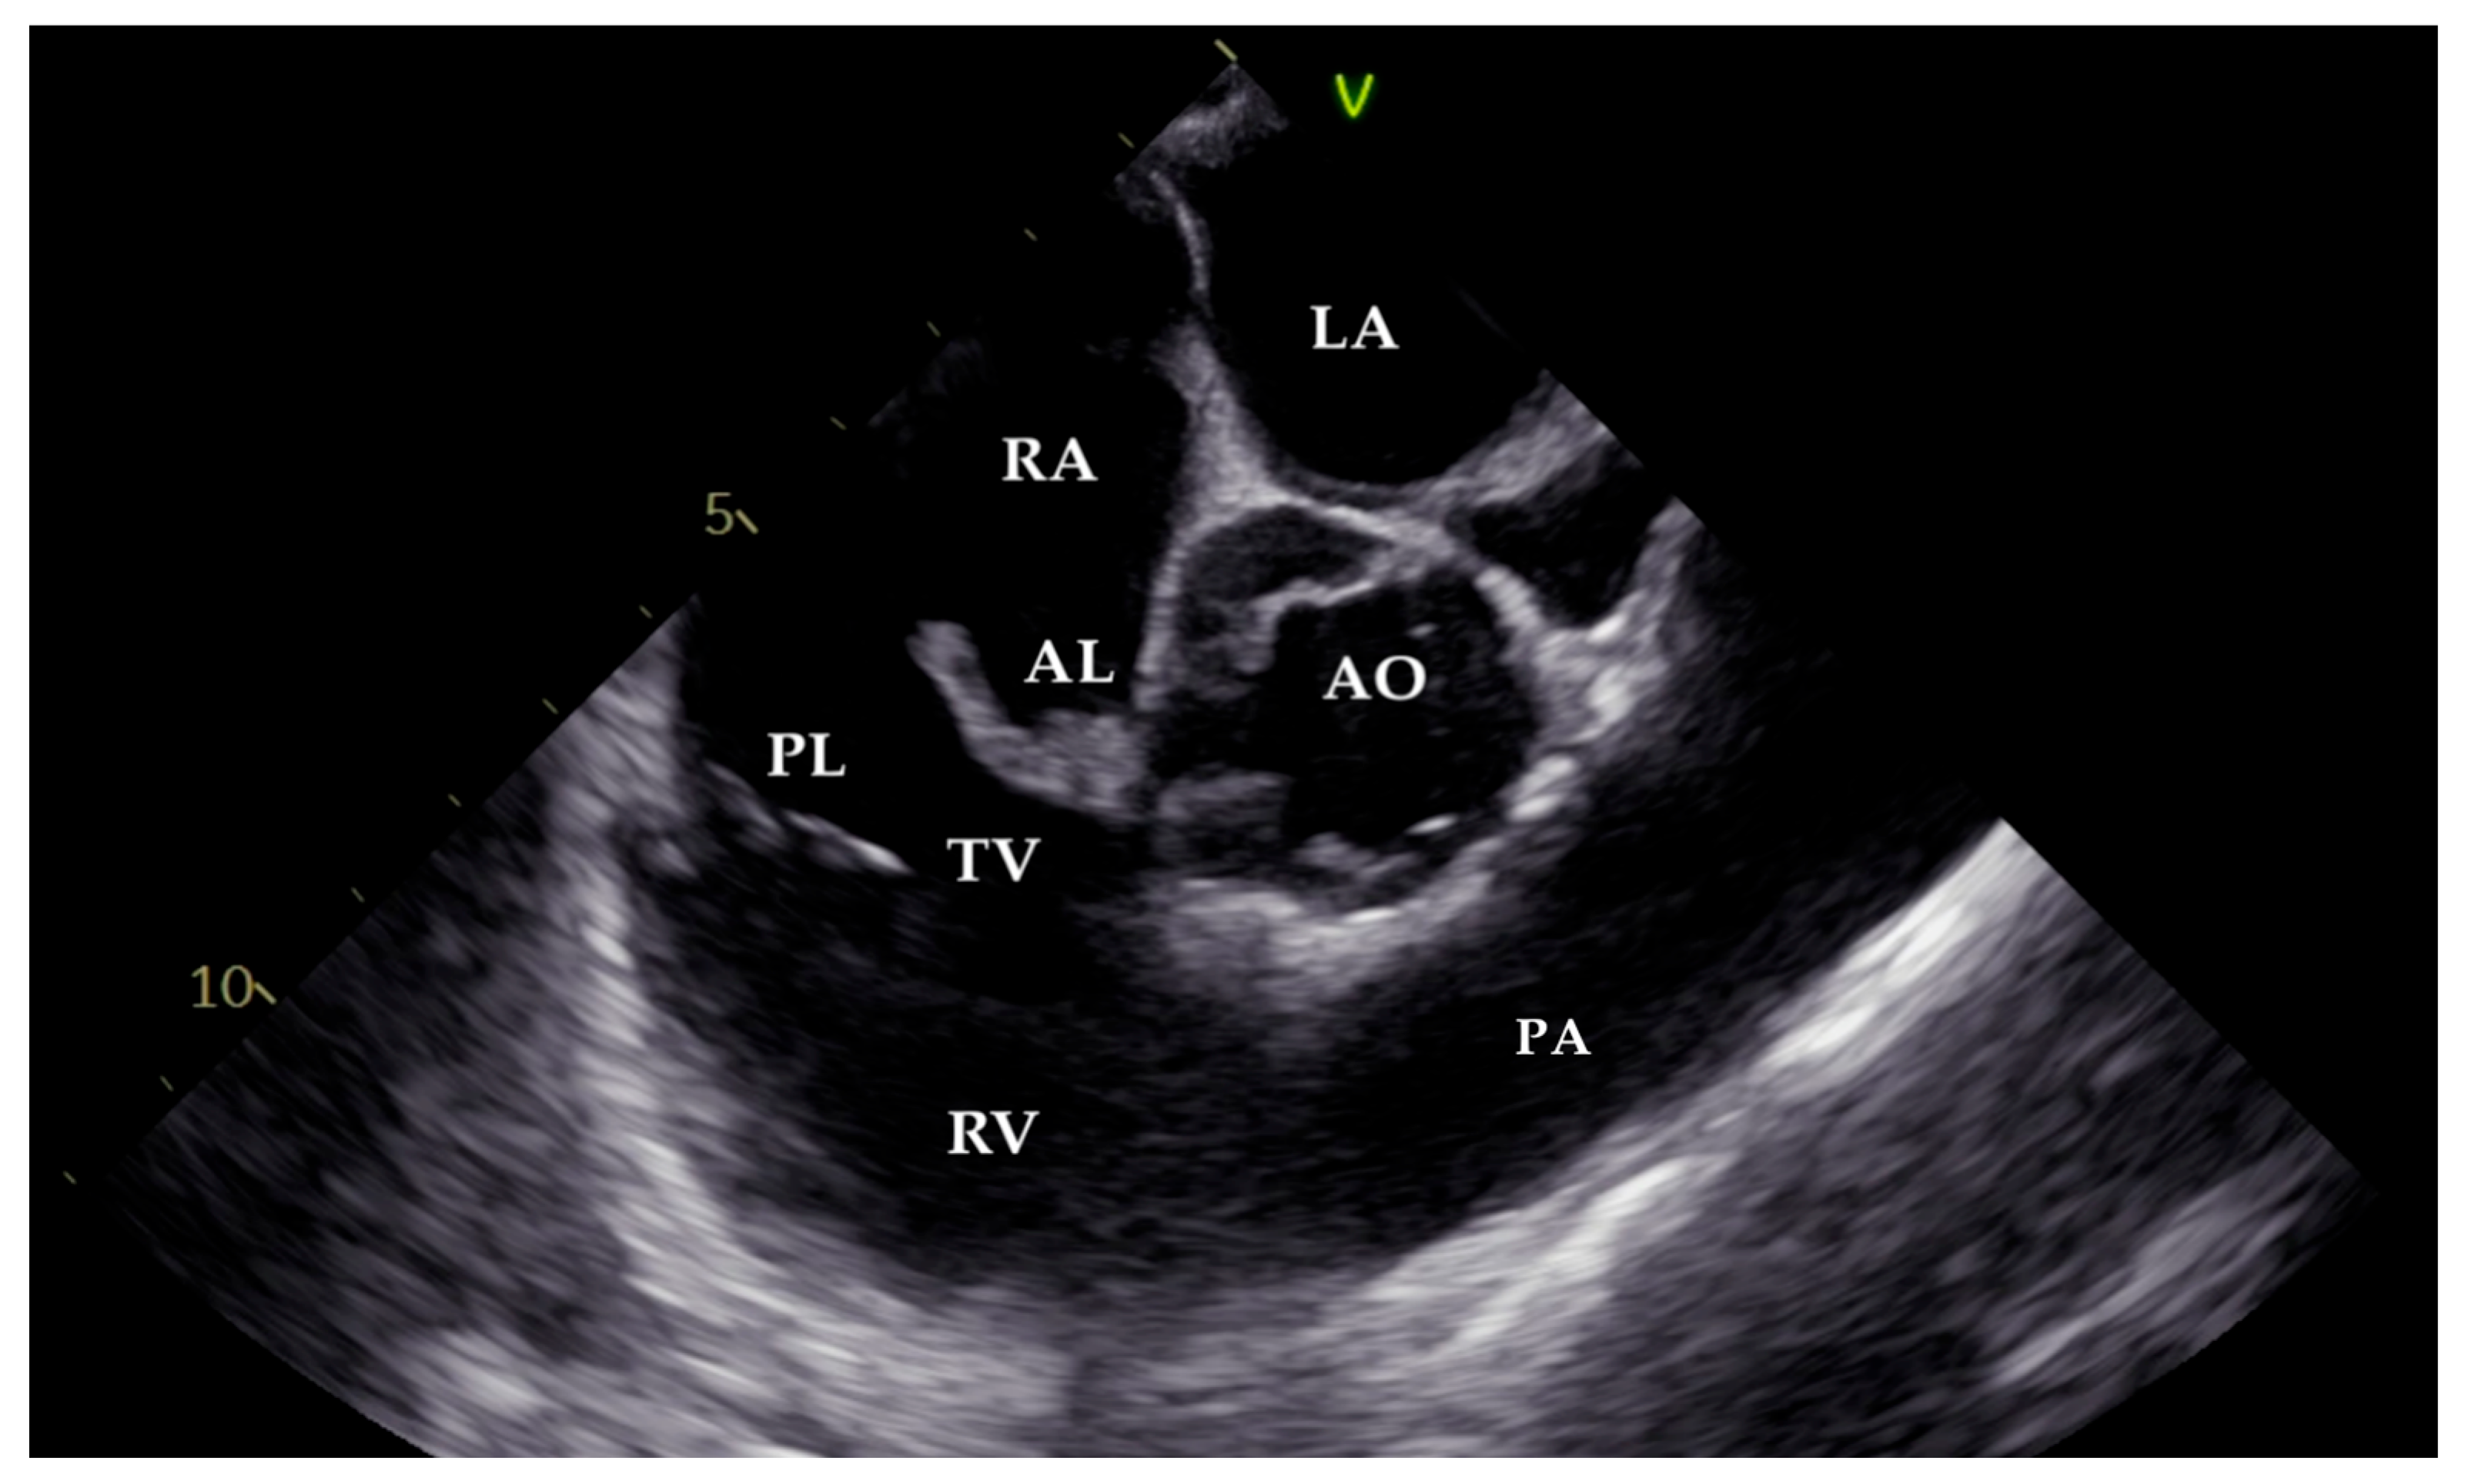

2. Case Presentation